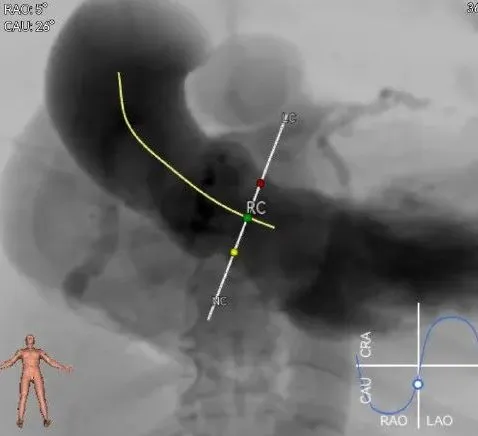

罗建方教授 广东省人民医院(点击查看专家详细简历) 设计本为临床需,耐久守护好芳华:任何医疗产品的设计初衷与最终归宿,都应落在 “临床获益” 这一核心上。尤其在 TAVR 领域,年轻患者预期寿命长,术后瓣膜的长期性能直接关乎其生活质量与生存预后。瓣膜耐久性问题,是落到临床实践中亟待突破的关键课题。传统瓣膜在长期使用中,可能因结构老化、功能退化等问题,难以满足年轻群体数十年的健康需求,二次手术风险也随之攀升。因此,产品设计必须直面这一临床痛点:通过材料革新增强抗钙化性能及生物相容性,以技术突破延长瓣膜有效使用寿命。此次临床应用的预装干瓣Prostyle A®是TAVR领域的革新理念,干瓣预期会为临床提供更耐久性的保障,实现了与临床需求的精准对接,为年轻群体的瓣膜治疗提供更坚实的保障。 李捷教授 广东省人民医院(点击查看专家详细简历) 干瓣技术求革新,性能兼顾护临床:干瓣的技术革新在创新的同时需要和临床实际需求深度耦合,兼顾TAVR术中的核心考量点。临床操作中,瓣膜能否顺利过弓,直接影响手术效率与安全性。Prostyle A®短瓣架设计及第二台阶的柔顺设计,术中操作丝滑;同时,瓣膜植入后的径向支撑力必须平衡得当,才能实现稳定锚定;释放后造影显示:瓣膜形态舒展,轻度瓣周漏,舒张压升高,冠脉开口未受影响;瓣周漏是影响术后效果的关键隐患,双层裙边设计通过多重密封机制降低反流风险,为患者长期获益筑牢防线。这些性能的协同优化,最终目的是让干瓣在临床中真正做到 “好用、耐用、安全用”,为患者预后提升提供坚实支撑。 患者病史 患者因 “活动后气促伴头晕 2 月” 入院。 现病史:2月前无诱因出现活动后气促,休息后缓解,伴头晕,夜间阵发性呼吸困难。超声检查发现:主动脉瓣重度狭窄并重度返流(跨瓣流速 4.3m/s,峰值压差 73mmHg);主动脉 + 冠状动脉 CTA 提示主动脉瓣显著钙化,升主动脉及分支粥样硬化,冠状动脉轻度狭窄(RCA 狭窄 30-40%)。 既往史:高血压病史 15 年,规律服药,血压控制稳定。 术前诊断:非风湿性主动脉瓣狭窄伴关闭不全(重度)、心功能 II 级(NYHA)、高血压病 2 级(高危)、冠状动脉粥样硬化。 术前CT 三叶瓣,瓣叶增厚中度钙化,右无交界钙化粘连,瓣环径25.1mm,LVOT 25.1mm,直筒型结构;窦部空间足够,升主未见增宽,瓣环水平夹角55°;冠脉开口位置佳,无冠脉风险;入路散在钙化、外周双侧入路无明显迂曲,双侧内径可、中分叉,左右侧均能够支持20F 大鞘通过。 造影角度及入路 右窦居中位RAO 5° CAU 26° 左冠切线位LAO 11° CRA 12° 手术策略 右侧股动脉为主入路,左侧为辅助入路;使用20球囊预扩,准备AV26瓣膜,冲洗口朝向3点钟方向送入输送系统性能,初始定位真实瓣环0位释放,最终锚定约瓣下3mm,工作位评估瓣膜稳定性与冠脉情况。 手术过程 根部造影 20mm 球囊预扩无明显腰征 术中使用26号瓣膜,瓣膜释放贴边迅速 80% 工作位观察瓣膜位置良好 释放后造影显示:瓣膜形态舒展,轻度瓣周漏,舒张压由术前30mmHg升为 60mmHg,冠脉开口未受影响。 术后超声:跨瓣流速降至1.6m/s,平均压差降至5 mmHg,心功能显著改善。 Prostyle A®预装干瓣——助力临床最优化解决方案: 1. 抗钙化与耐久性:Micro-EX™专利技术提升瓣膜抗钙化能力,适配患者瓣叶中度钙化的解剖特点,为长期疗效提供保障。 2. 柔顺过弓与精准定位:短瓣架设计 + 远端超滑涂层,确保患者输送系统过弓顺畅;瓣架流入端微直筒设计,让定位贴边更迅速,减少了手术时间; 3. 80% 可回收设计:便于术中调整观察,减少起搏时间,从而减少并发症。 4. 简化手术流程:预装设计缩短操作时间,20F 大鞘兼容外周入路,降低血管损伤风险。